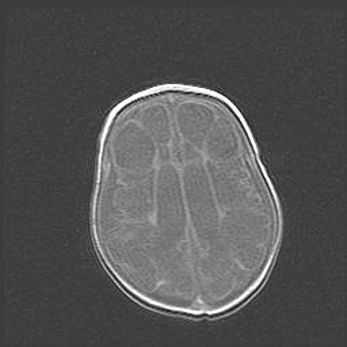

Церебральная ишемия II.

Возраст: 5 дней

Вес: 3400 г

Пол: женский

Окружность головы: 35 см

Срок гестации: 39 недель

Церебральная ишемия – это заболевание, характеризующееся недостаточностью (гипоксией) либо полным прекращением (аноксией) снабжения мозга кислородом по причине закупорки одного или нескольких сосудов. Это приводит к  что метаболическим расстройствам различной степени тяжести в тканях головного мозга, развитию коагуляционных некрозов и гибели нейронов.